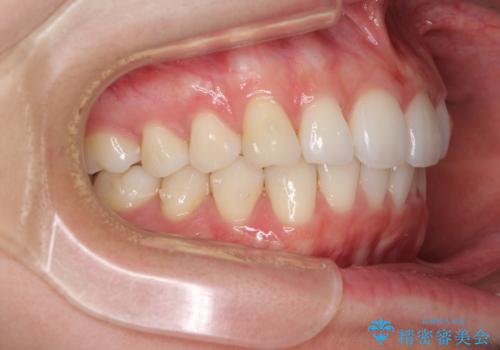

- 上下前歯の叢生を気にして来院された患者様です。

以前矯正をした後戻りということで、歯列不正はそれほど大きくなかったため、インビザライン・ライトを用いて矯正治療を行うこととしました。

前歯のデコボコが残っており、シミュレーション通りに動いていない部分がありましたが、再矯正であることやご本人の満足いくところまでデコボコが改善されたとのことで、治療を終了することとしました。